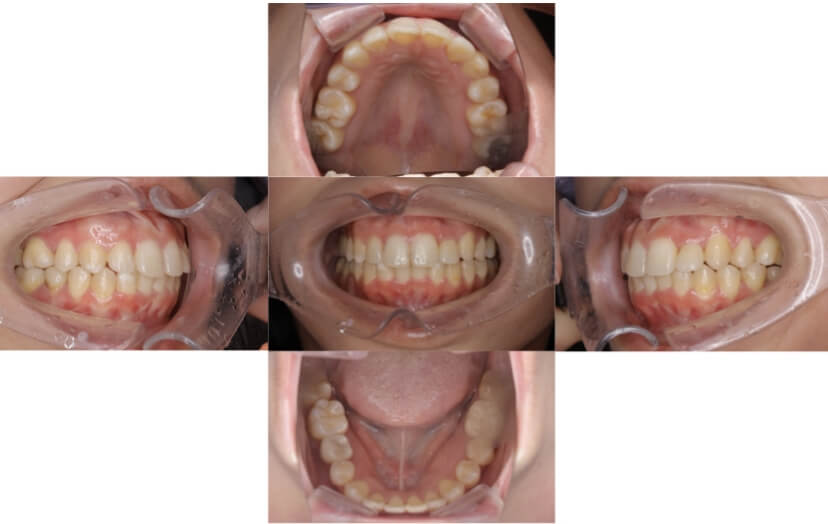

BEFORE

AFTER

症例3

叢生

抜歯

ブラケット矯正

上下顎叢生(上下の前歯のガタガタ)のケースです。

装置はラビアル(上下表側)で、上下顎の小臼歯を4本抜歯を行っています。抜歯したスペースを使って、上下の前歯の後方移動と叢生(ガタガタ)の改善を行っています。

主訴 八重歯を治したい。

年齢・性別 25歳 女性

お住まいの地域 神奈川県川崎市

治療方針 抜歯スペースを利用して上前歯の叢生(ガタガタ)の改善

抜歯部位 上下顎左右第一小臼歯

使用装置 ラビアル(上下表側)、顎間ゴム

治療期間 1年11か月

治療回数 16回

リテーナー クリアリテーナー